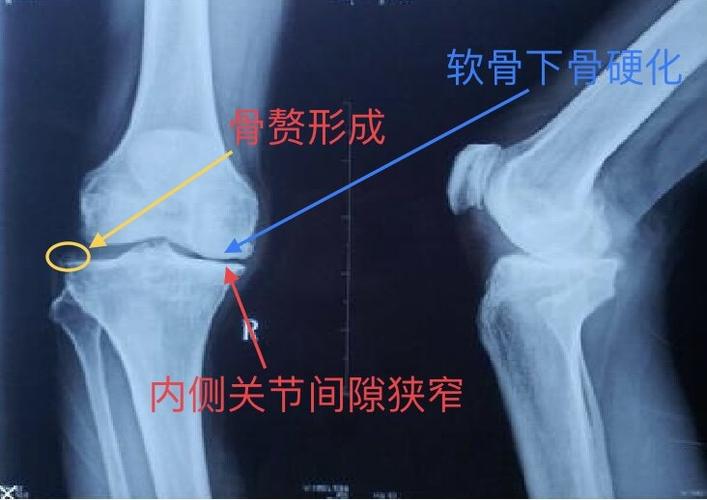

骨关节炎示意图,骨关节炎膝关节

膝关节骨性关节炎示意图

骨关节炎膝关节

骨关节炎x线